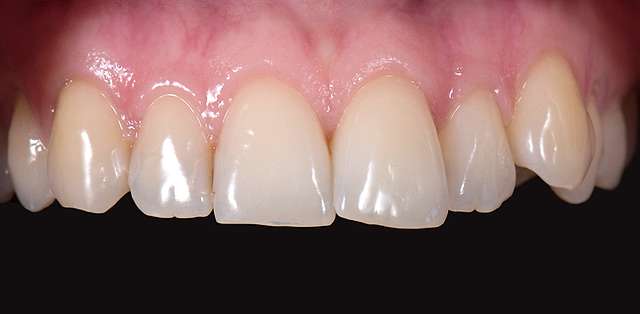

Here we had to deal with a significantly deviated midline, needed to bring one canine on the arch and basically realign teeth on both arches. To finish we did some composite details. When existing teeth have naturally beautiful shapes, orthodontics is many times a superior alternative to prosthetic treatment. It has one disadvantage: requires more time.